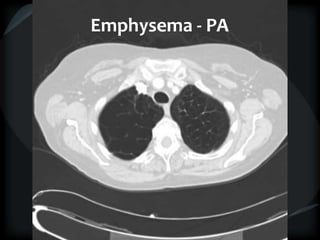

Emphysema - CL

Emphysema - PA

Hyperlucency

Centrilobular emphysema

Paraseptal emphysema

Panacinar emphysema